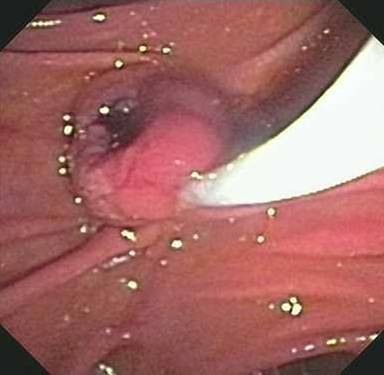

The patient was referred to the University of Colorado to establish tissue diagnosis and for an attempted endoscopic resection given his age and comorbidities. On repeat ERCP, an ampullary mass was identified involving the major papilla (Figure 1). A localized distal biliary stricture was also found which did not have the appearance of intraductal growth of an ampullary mass. Endoscopic ultrasound confirmed the presence of the ampullary mass causing a stricture (mass 2.2 cm in largest diameter; Figure 2). The stricture was in the very downstream common bile duct, felt to be entirely within the intra-duodenal portion, and EUS showed no definite submucosal invasion. Endoscopic biopsies were suspicious for adenocarcinoma, but without definite invasion; it was not felt that brushings would add any useful information at this point. After a lengthy discussion of treatment options, the patient elected for an attempt at endoscopic ampullectomy rather than proceeding directly to surgery. Endoscopic ampullectomy was performed with a polypectomy snare in multiple segments (Figure 3). Histologic analysis demonstrated periampullary/duodenal dysplasia (adenoma) associated with invasive carcinoma limited to the ampulla. Immunohistochemistry demonstrated positive staining for CK20 and CDX2 and negative staining for CK7. Based on the combined findings of duodenal dysplasia and immunoreactivity for CK20 and CDX2, the carcinoma was classified as intestinal-type. Invasive carcinoma was widely present at the cauterized tissue edges. No lymphovascular invasion was identified.

Figure 3. Ampullectomy with snare was performed. |